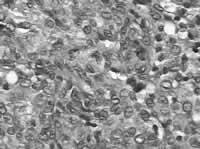

胸腔镜下肺活检普通病理(见图3):可见大小不等的结节,结节内见增生的郎格罕组织细胞,符合郎格罕细胞组织细胞增生症。免疫组化:CD1a阳性,CD68阳性,电镜检查:肺泡间隔及肺泡腔内可见大量组织细胞浸润及渗出,但胞浆中未找到特征性的Birbeck颗粒。

图3

病理HE染色